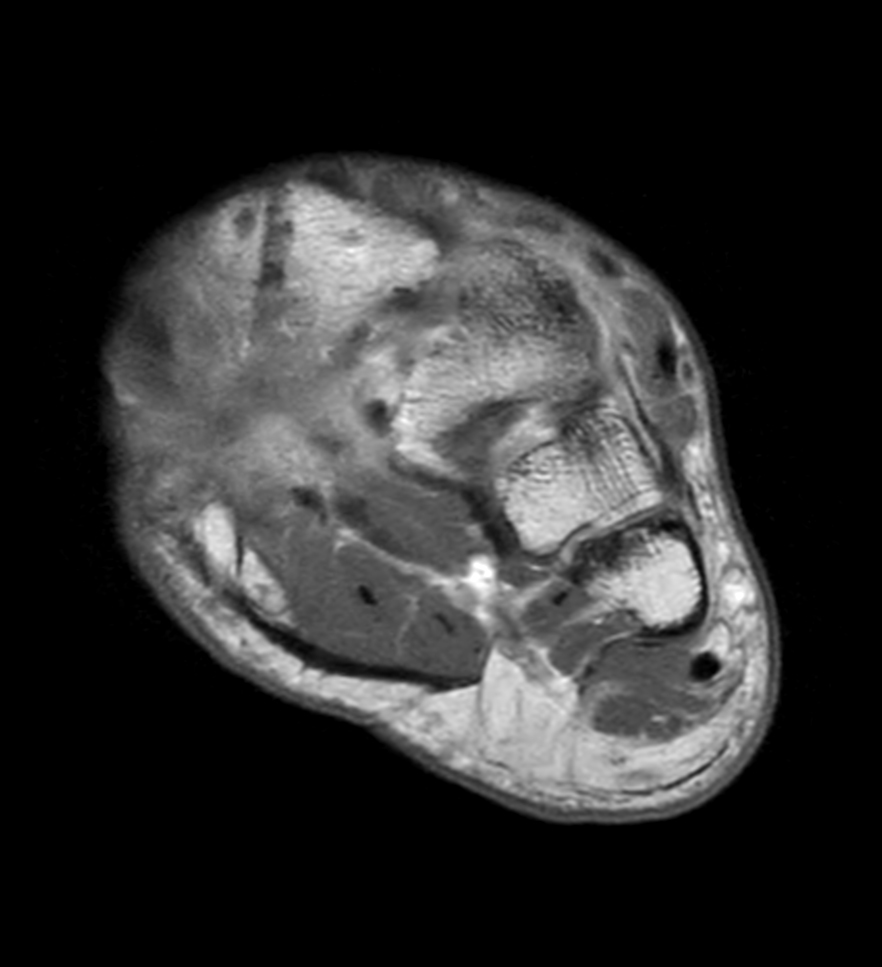

Ankle/Foot imaging post-amputation

Patient with partial amputation of the foot

3D VIEW PDw SPAIR - Axial reformat

Axial T1w mDIXON XD TSE with gado (Water only)

Axial T1w mDIXON XD TSE with gado (In Phase)